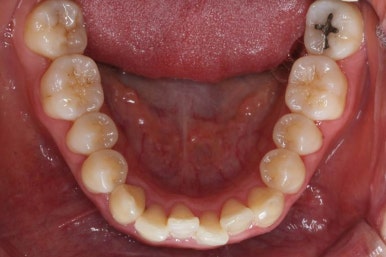

마찬가지로 부산설측교정 키다리아저씨치과에서 처음 내원하셨을 당시의 입안 모습입니다.

어금니쪽은 특별히 이상이 없었고, 위아래 앞니만 삐뚤한 상태였습니다.